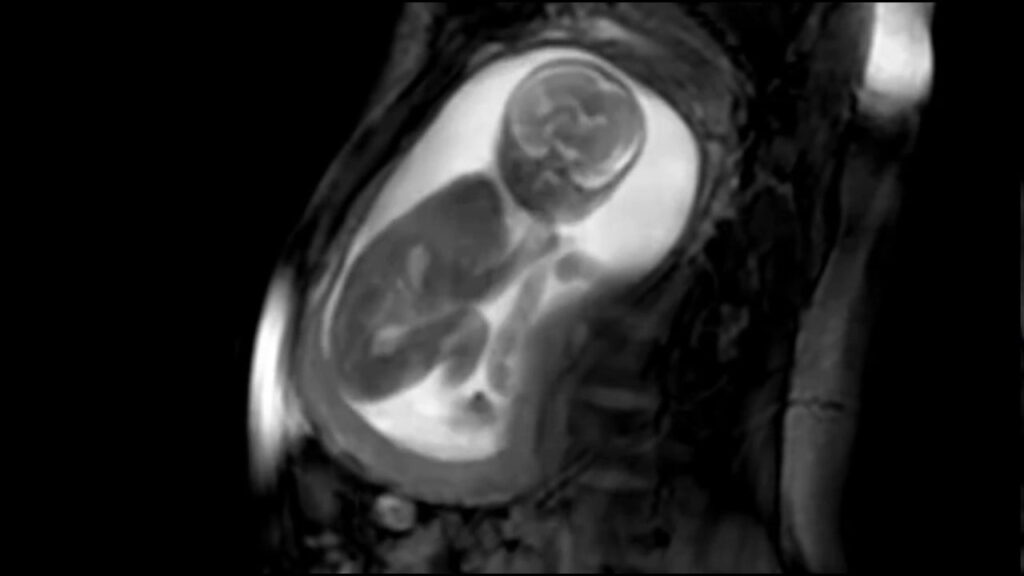

Czy mogę poddać się badaniu MRI, jeśli jestem w ciąży?

Niestety, nie ma prostej odpowiedzi. Przed badaniem należy poinformować lekarza o ciąży. Przeprowadzono stosunkowo niewiele badań dotyczących wpływu rezonansu magnetycznego na ciążę. Jednak wytyczne opublikowane w 2016 roku rzuciły więcej światła na tę kwestię.

Zazwyczaj lekarze nie zalecają stosowania materiału kontrastowego u kobiet w ciąży.

Skany MRI powinny być ograniczone w pierwszym trymestrze ciąży, chyba że informacje są uważane za niezbędne. Skany MRI w drugim i trzecim trymestrze są bezpieczne przy natężeniu 3,0 tesli (T) lub mniejszym. Tesla jest miarą siły magnetycznej.

Wytyczne stwierdzają również, że ekspozycja na MRI w pierwszym trymestrze ciąży nie jest związana z długoterminowymi konsekwencjami i nie powinna budzić obaw klinicznych.